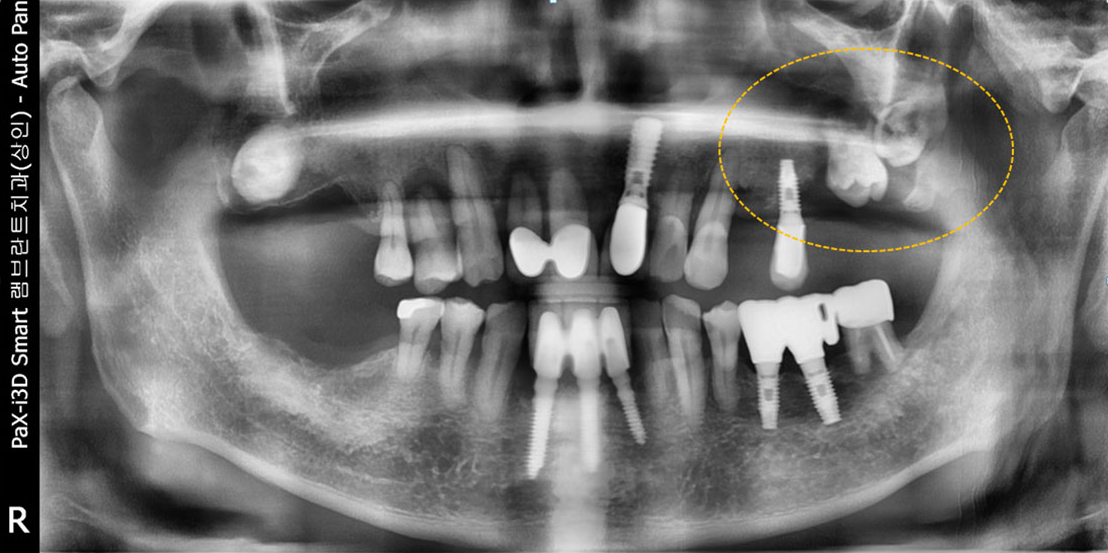

윗턱뼈에 사랑니가 매복된 경우

매복된 제2 대구치

매복된 사랑니

견고한 금속 차폐막 적용

치료 전

치료 후윗턱뼈 공기주머니에 뼈이식

치료 후